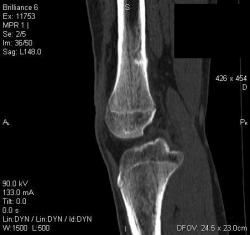

Мальчик 15 лет. Несколько месяцев назад начали беспокоить боли в коленных суставах. Травмы не было. Ребёнку был выставлен диагноз: болезнь Шлаттера, назначено лечение. На фоне лечения отмечалось значительное усиление болей, боли локализовались в левом коленном суставе. При дообследовании выявлена следующая рентгенологическая картина. Наши рентгенологи настаивают на срастающемся переломе. Но: 1) перелом без травмы? 2) бедро так не ломается

В голову приходит остеомиелит или опухоль.

Линейный периостит, уже должен был рентгенологов насторожить.

Локальный гиперостоз, выраженный болевой синдром, структура губчатого вещества диафиза не изменена наводит только на остеойд-остеому.

Я бы на первое место поставила патологическую перестройку, так называемый, стрессовый перелом. Мальчик чем-нибудь занимается?

Согласна с Ola-la - рентгенологическая картина более всего соответствует стрессорному перелому, хотя для него характерна локализация в б/берцовой кости. Меня однако, смущает и настораживает клиника - это как раз тот случай, когда я бы не дала 100% гарантии, что так не может манифестировать остеосаркома... Поскольку другие методы (МРТ, сцинтиграфия) вряд ли помогут, я бы взяла пациента на короткое ( 2недели - месяц) динамическое наблюдение.

Да, на мой взгляд, состояние после обычного "травматического перелома" (трещина), не думаю, что имел место "патологический перелом", так как костная ткань "патологически изменена" минимально. "Перистальная реакция"локальная тоже есть, на КТ "локальная  зона склероза" - все это свидетельствует именно об этом. Хотя в памяти у меня хорошо отложился Ваш последний случай о локальном утолщении кортикального слоя, когда "яйца в гнезде" еще не было. То, что анамнестически "травмы не было" - ничего не значит. Вы, по всей видимости, тоже часто встречались с такими случаями, когда ребенок не акцентировал внимание на "травме", как таковой, хотя клиника есть, боль есть. Конечно, рентгенограммы - не дай бог - ни скиалогии, ни структуры.

Буквально заключение гистологов передать не могу (мой недочет, нужно было сразу выложить на сайтОй-ой-ой), но приблизительно помню - данных за специфический процесс нет, картина консолидирующегося перелома.

Так что, по всей видимости, это действительно был стресс-перелом. Который крайне редко встречается. Хоть статейку в журнал пишиУлыбаюсь.